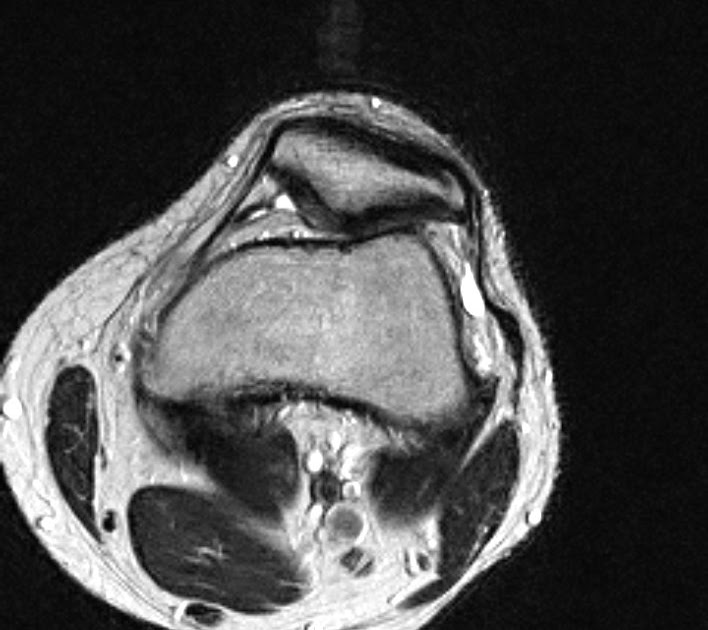

resonance image revealing moderate lateral patellar tilt and What Does A Lateral Patellar Tilt Mean lateral patellar compression syndrome is the improper tracking of the patella in the trochlear groove generally caused by a tight lateral. lateral release is a minimally invasive surgery used to correct an excessive patellar tilt. This is when the patella tilts slightly outwards so it can’t sit flat in the groove and therefore rubs against the bone; It. What Does A Lateral Patellar Tilt Mean.